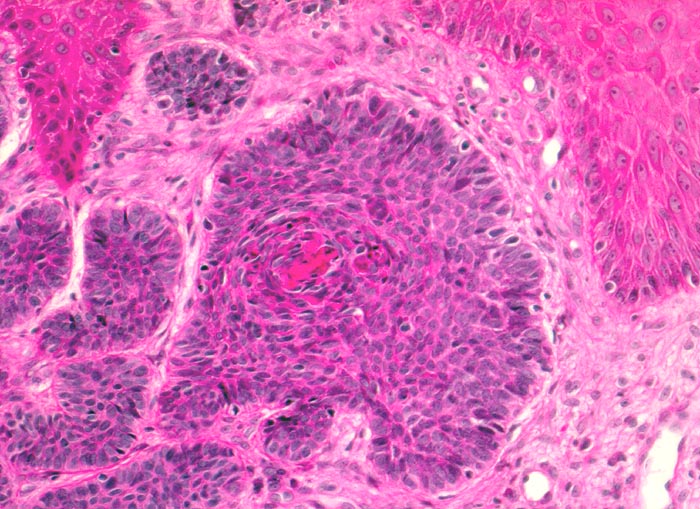

PathoPic – image database / PathoPic ID 5102 - Basaliom

Basaliom

maligner Tumor

Haut, Kopf

Ein Teil der Tumorzellplatten zeigt im Zentrum eine angedeutete Verhornung. Die zytoplasmaarmen Tumorzellen sehen sehr ähnlich aus wie die Basalzellen der Epidermis.

Derber weisser, leicht erhabener Knoten an der Nase.

Histologie

200